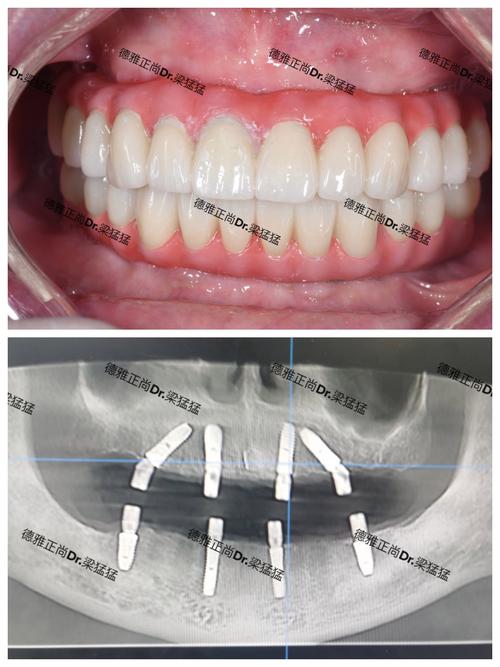

北京永康口腔注重个性化方案设计,会根据患者的牙槽骨密度、咬合习惯、面部美学需求等,制定“一人一策”的种植方案,对于牙槽骨萎缩的患者,可采用骨增量技术(如植骨、上颌窦提升)重建骨条件;对于全口缺牙患者,All-on-4/6即刻负重技术可实现当天种牙、当天戴牙,快速恢复咀嚼功能。

戴牙冠:种植体植入后3-6个月(骨愈合期),通过基台连接牙冠,牙冠材质包括全瓷、烤瓷等,其中全瓷牙冠色泽、通透度接近天然牙,美观度更佳。